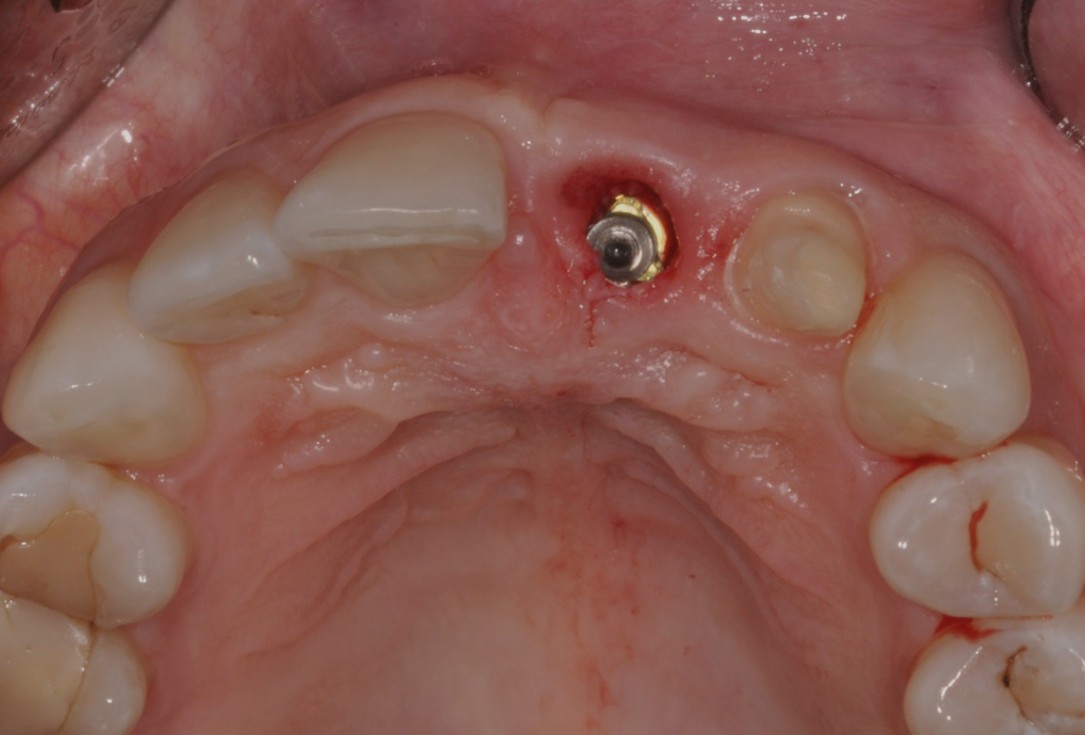

02/16 - Situation before extraction, occlusal view